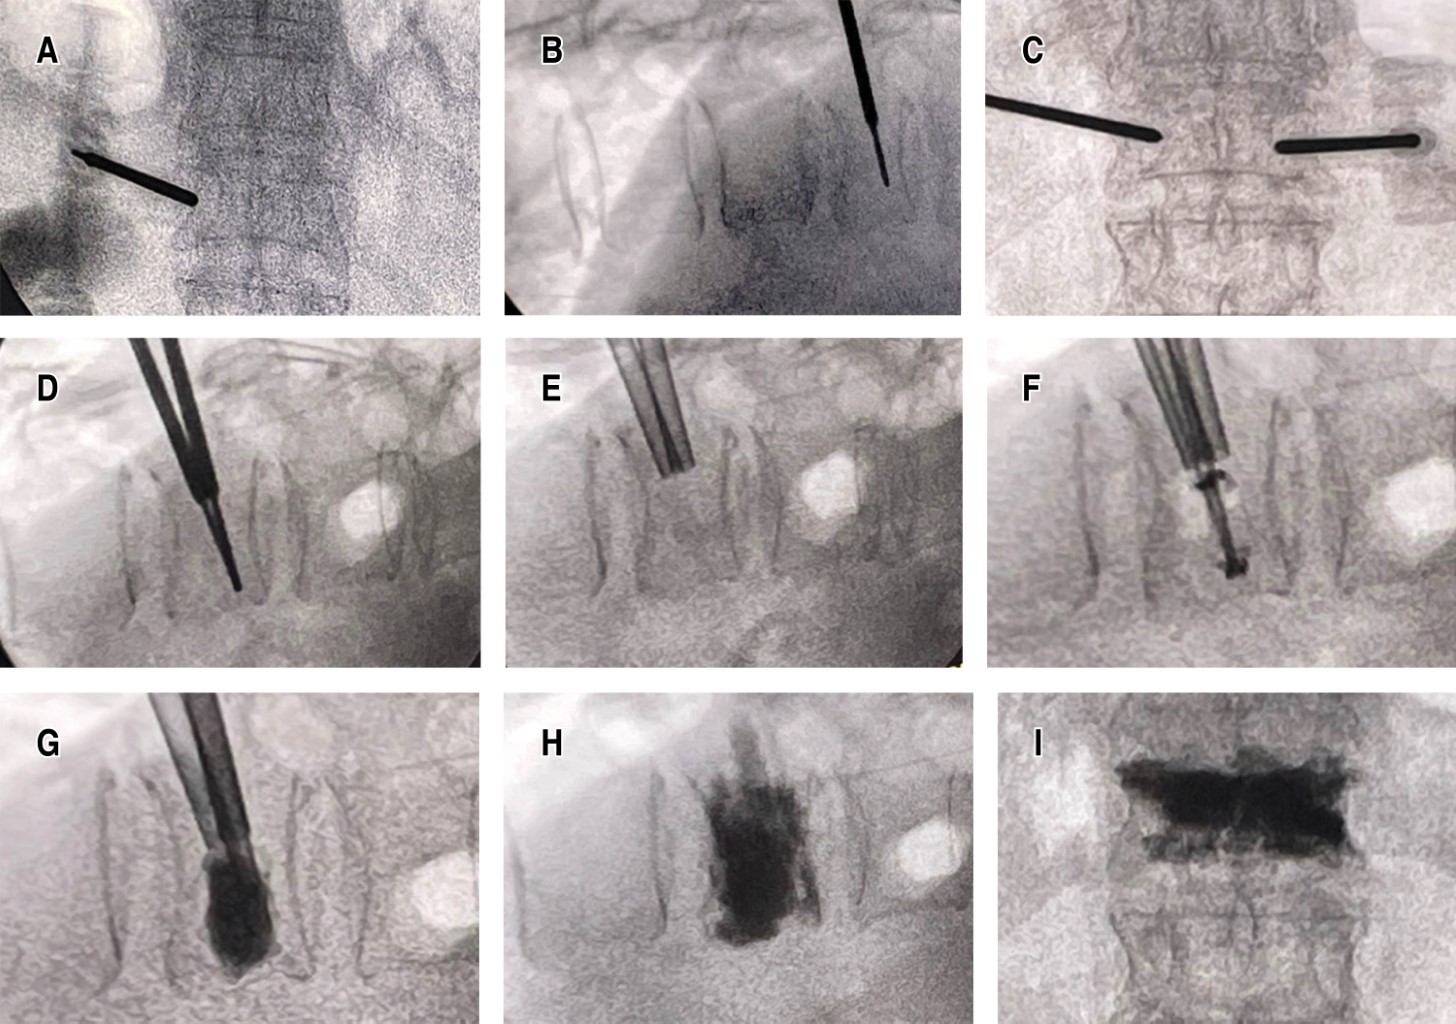

El procedimiento quirúrgico se estandarizó para todos los participantes. La cifoplastía se realizó con el paciente bajo anestesia general o sedación profunda según el criterio anestésico individualizado. La técnica implicó la inserción percutánea de cánulas a través de abordaje posterior bilateral hasta alcanzar la vértebra afectada, seguida de inflado de balones específicos para la restauración de la altura vertebral y estabilización del cuerpo vertebral con cemento radiopaco (polimetilmetacrilato, PMMA). Posteriormente, de manera inmediata tras concluir la cifoplastía, se aplicó la técnica de RF-P en las facetas articulares correspondientes al nivel tratado. Este procedimiento fue realizado utilizando un equipo especializado de RF-P, ajustado a parámetros estandarizados (temperatura máxima de 42 °C, pulsos con duración de 20 ms y una pausa de 480 ms durante cuatro minutos por cada faceta articular tratada) (Figuras 1 y 2).

Tradicionalmente, el tratamiento de las fracturas vertebrales por compresión ha sido conservador, enfocado en el reposo, la administración de analgésicos, la terapia física y la utilización de ortesis para reducir el dolor y facilitar la movilidad temprana. Sin embargo, el manejo conservador frecuentemente no logra resultados satisfactorios en términos de alivio del dolor y recuperación funcional a largo plazo, especialmente en pacientes con fracturas severas o múltiples.16,17 Esto ha llevado al desarrollo y creciente adopción de técnicas quirúrgicas mínimamente invasivas que buscan estabilizar rápidamente la vértebra afectada, reducir el dolor de manera inmediata y facilitar una recuperación funcional precoz y sostenida. Entre estas técnicas quirúrgicas, la vertebroplastía y la cifoplastía han ganado amplia aceptación por su eficacia comprobada en estabilizar la estructura vertebral fracturada y proporcionar un alivio rápido del dolor (Figura 4). La cifoplastía, en particular, ha demostrado ventajas adicionales sobre la vertebroplastía, como la recuperación parcial de la altura vertebral y menor riesgo de complicaciones asociadas con la fuga de cemento hacia los tejidos adyacentes.18,19 Aunque la cifoplastía ofrece resultados positivos en la mayoría de los casos, persiste una proporción considerable de pacientes que experimentan dolor residual postoperatorio, frecuentemente vinculado con patologías de las articulaciones facetarias adyacentes, las cuales suelen verse afectadas directa o indirectamente por el proceso de fractura o por alteraciones biomecánicas secundarias a la fractura y su tratamiento. Este dolor facetario residual representa un desafío clínico significativo, dado que limita considerablemente la recuperación funcional óptima.20,21 La necesidad de abordar este tipo específico de dolor residual ha motivado la exploración de estrategias complementarias que puedan integrarse a la cifoplastía para optimizar el control del dolor inmediato y sostenido en el periodo postoperatorio. Dentro de estas estrategias complementarias, la RF-P aplicada a las facetas articulares ha emergido recientemente como una técnica innovadora y prometedora, debido a su capacidad para producir neuromodulación efectiva sin destruir irreversiblemente las estructuras nerviosas implicadas.22,23